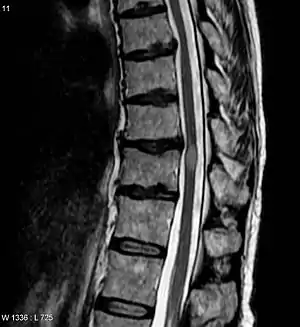

| A MRI showing an area of transverse myelitis, which is lighter, oval shape at center-right. The person recovered after 3 months. | |